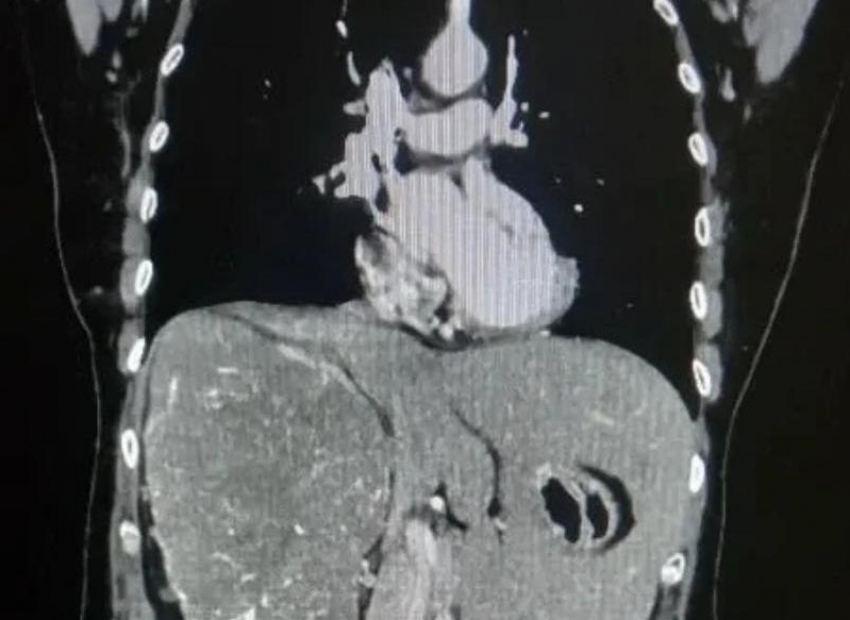

Врачи Волгоградского областного онкологического диспансера провели сложную операцию пациентке с гигантской опухолью почки. Новообразование достигло таких размеров, что сместило внутренние органы: печень оказалась вытеснена из правой части брюшной полости в левую.

Женщина долгое время жаловалась на тупую боль в пояснице и чувство тяжести в животе. После обследования с помощью компьютерной томографии врачи обнаружили крупную опухоль, которая практически полностью заняла правую сторону брюшной полости. Исследования показали, что функция правой почки была почти полностью утрачена. Размер новообразования составил более 20 сантиметров. Медики приняли решение о проведении операции. Из-за больших размеров опухоли выполнить вмешательство малоинвазивным способом было невозможно, поэтому хирурги провели открытую операцию — радикальное удаление правой почки.

Операцию выполнила команда специалистов онкоурологического отделения. Несмотря на сложность случая, хирургам удалось полностью удалить опухоль. По результатам гистологического исследования был подтверждён диагноз — светлоклеточная карцинома. При этом новообразование не успело прорасти в соседние органы, а лишь сильно сместило их, сообщили в пресс-службе облздрава Волгоградской области.

Послеоперационный период прошёл без осложнений. Уже через восемь дней пациентку выписали под наблюдение врачей амбулаторной службы. Специалисты отмечают, что рак почки часто долго развивается без выраженных симптомов. Именно поэтому врачи напоминают о важности регулярных медицинских осмотров и диспансеризации, которые позволяют выявлять заболевания на ранних стадиях.